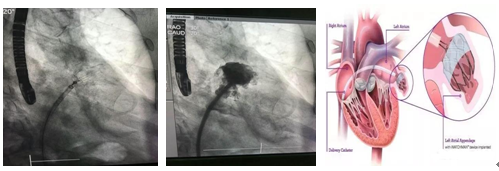

2018年6月14日,我院心血管内科凌智瑜副教授在多学科合作下再次完成1例左心耳封堵术,标志着我院心内科在对房颤患者的治疗方式取得更大的进